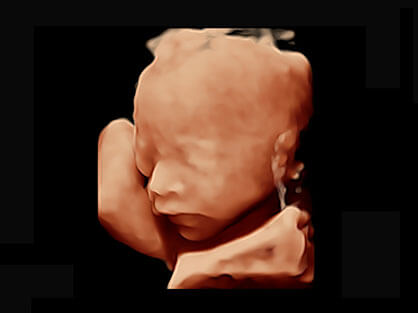

临床图